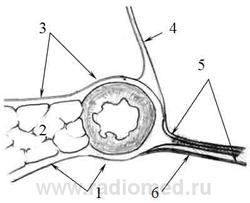

Рисунок 2.6. Правая порция связки нижнегоризонтальной ветви ДПК (поперечный срез на уровне перехода нисходящей части ДПК в нижне-горизонтальную - схема)

1 - позадипанкреатическая фасция

2 - головка поджелудочной железы

3 - предпанкреатическая фасция

4 - корень брыжейки поперечноободочной кишки

5 - слияние вышеперечисленных фасций и фасции Toldti – правая порция связки нижнегоризонтальной ветви ДПК

6 - фасция Toldti